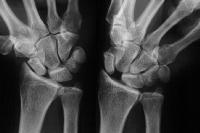

Palmar flexion of the scaphoid, lunate dorsiflexion.

Scapholunate diastasis.

Click for larger image